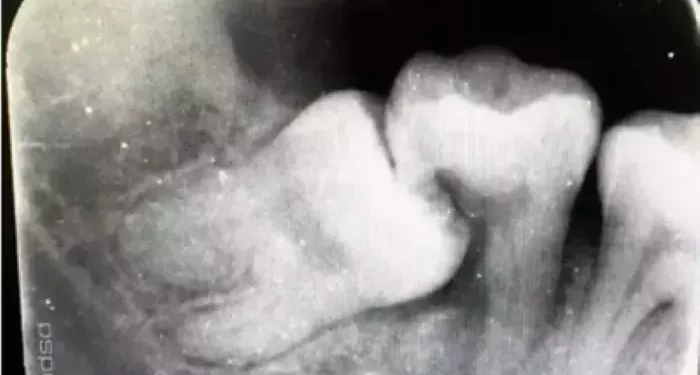

X-rays: These images help identify cavities that are not visible to the naked eye, especially those below the surface.